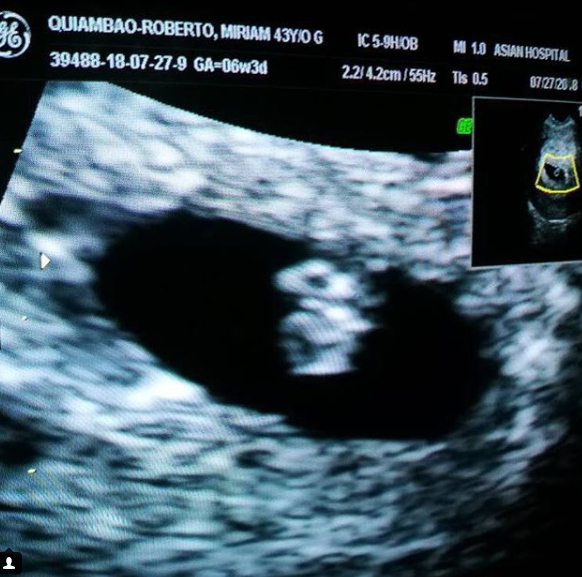

Former Miss Universe 1999 first runner-up Miriam Quiambao-Roberto shared a good news on Instagram that she is nine weeks pregnant.

Quiambao, 43, says that she and her husband Ardy Roberto, author and a motivational speaker, have been praying for a child for four years. The ecstatic mother-to-be showed on IG a sonogram taken at the Asian Hospital and Medical Center in Muntinlupa City. She even gave the hashtag "miracle baby" for the baby in her womb because she "conceived naturally."